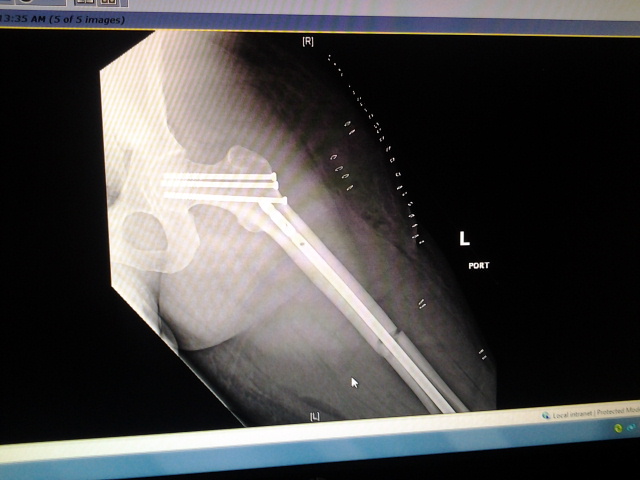

So... To start, I had a motorcycle accident and broke my leg in two places. They had to insert a rod and a bunch of screws in. But I think I had nerve damage. How I know? Well the outside of both my legs to the small toes are numb. Not totally, I have feeling. But they're numb.

I had the accident on 4-7-14. Been non-weight bearing on my left leg since.

Attachment:

2014-04-10 08.08.20.jpg

2014-04-10 08.08.20.jpg [ 84.72 KiB | Viewed 6295 times ]

Just don't ask me how my bike fared :/